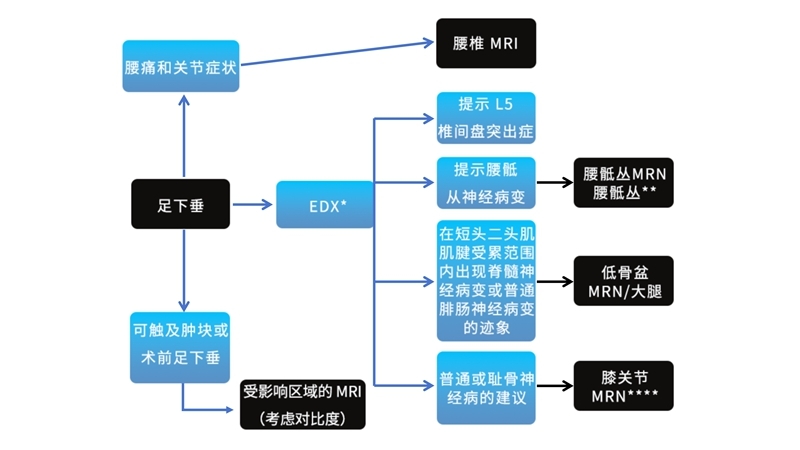

足下垂的特征性电诊断结果

L5神经根瘫的诊断

主要可通过病史、症状、体征、影像学检查:MRI和特殊检查:EDX Testing确诊,另外还需注意鉴别诊断。

疾病诊断流程